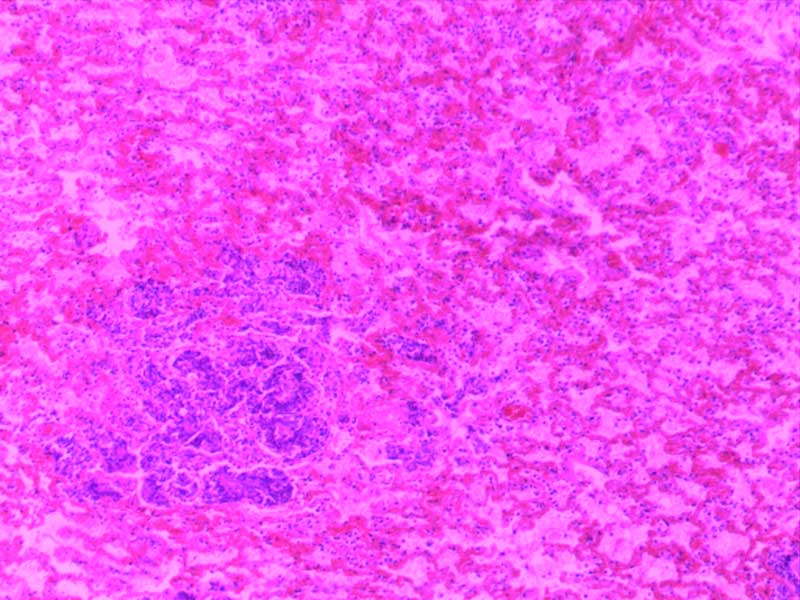

绒毛膜癌-10倍

肉芽组织-10倍

乳头状瘤(膀胱)4倍

乳腺癌-4倍

乳腺癌-10倍

神经鞘瘤4倍

神经鞘瘤-10倍-(2)

神经鞘瘤-10倍

大叶性肺炎(红肝期)10倍

大叶性肺炎(红肝期)-10倍

大叶性肺炎(灰肝期)-4倍

大叶性肺炎(灰肝期)-10倍